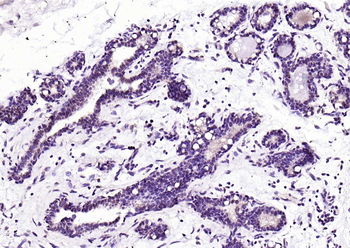

RARB Rabbit Polyclonal Antibody [orb11327]

FC, ICC, IF, IHC-Fr, IHC-P, WB

Bovine, Canine, Gallus, Porcine, Rat

Human, Mouse

Rabbit

Polyclonal

Unconjugated

50 μl, 100 μl, 200 μlTIG2 Rabbit Polyclonal Antibody [orb11481]